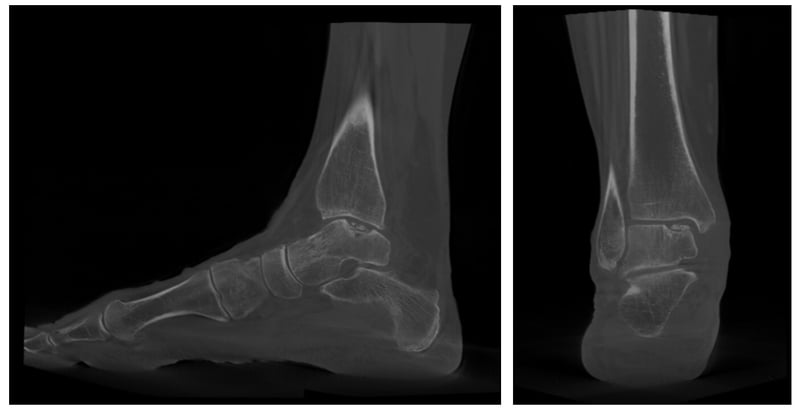

La TAC in carico, infatti, offre la possibilità di ottenere una misura affidabile della lesione, ma anche di andarne a misurare la reale forma, grazie a strumenti associati a intelligenza artificiale. Apprezzare la forma della lesione permette di essere ancora più precisi e di scegliere la tecnica che permetta la ricostruzione anatomica più efficace associando tecniche diverse di rigenerazione in base al caso.

Il nostro gruppo ha avviato questo filone di ricerca descrivendo come andare ad individuare la forma della lesione, misurarne l’area e guidare il paziente ed il chirurgo nella scelta terapeutica.

Efrima B, Dahmen J, Barbero A, Benady A, Maccario C, Indino C, Kerkhoffs G, Usuelli FG. Enhancing precision in osteochondral lesions of the talus measurements and improving agreement in surgical decision-making using weight-bearing computed tomography and distance mapping. Knee Surg Sports Traumatol Arthrosc. 2024 Jul;32(7):1871-1879. doi: 10.1002/ksa.12172. Epub 2024 Apr 9. PMID: 38591657.